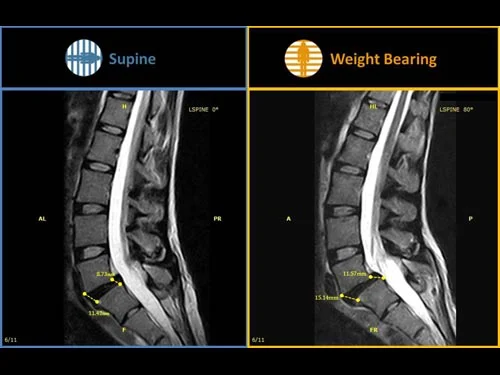

두번째 사진을 봅시다.

Supine 상태에서 디스크 팽륜 정도로 진단받은 환자가 있다고 합시다. 그런데 신경학적 증상과 통증이 심하다면 증상과 영상이 매치가 잘 안되겠지요?

그런데 우측의 영상을 보면 그 이유를 알 수 있습니다. Weight Bearing 시에 탈출된 volume이 늘어나면서 신경을 압박하고 통증을 증가시키고 있었던 것입니다.